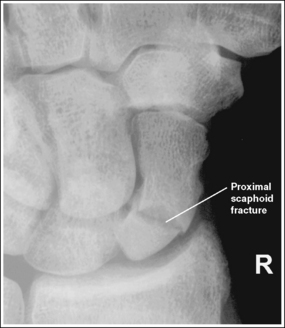

• Three areas of the scaphoid may be fractured: the waist, which sustains approximately 70% of the fractures; the distal end, which sustains 20% of the fractures; and the proximal end, which sustains 10% (Figure 4-47). Because scaphoid fractures can be at different locations on the scaphoid, precise positioning and central ray angulation are essential to obtain the optimum demonstration of this bone.

• Demonstrating fractures of distal and proximal scaphoid. When a fracture is suspected because of persistent pain and obliteration of the fat stripe but has not been demonstrated on routine images, it may be necessary to use different angles to position the central ray parallel with these fractures sites (Figure 4-48). A decrease of 5 to 10 degrees in central ray angulation better demonstrates the proximal scaphoid. Compare Figures 4-49 and 4-50. These PA axial projections demonstrate a proximal fracture. Figure 4-49 was taken with the typical 15-degree proximal angle, and Figure 4-50 was taken with a 5-degree proximal angle. Note the increase in fracture line visualization in Figure 4-50. Increase the central ray angle by 5 to 10 degrees, with a maximum of 25 degrees, to demonstrate a distal scaphoid fracture best (Figure 4-51). Angulations more than 25 degrees project the proximal second metacarpal onto the distal scaphoid, obscuring the area of interest (see Image 57).

Figure 4-49 PA axial (scaphoid) projection taken with a 15-degree proximal central ray angle demonstrating a proximal scaphoid fracture.

Figure 4-50 PA axial (scaphoid) projection taken with a 5-degree proximal central ray angle demonstrating a proximal scaphoid fracture.